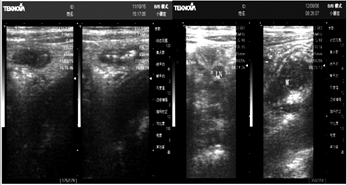

超声可见肚脐周围右下腹数个椭圆形低回声结节,边界清楚,形态规整,内部图像很典型,不过后位阑尾和肥胖人

阑尾炎的超声确诊,一直是底层超声盲肠后位,能超声找到阑尾顶级指向是阑尾超声最高地步。

[摘要]目的 探讨急性阑尾炎的超声图像特征。方法 对116例我院手术病理证实的阑尾炎的声像图进行回顾性分析,

急性阑尾炎的超声图像分析,急性阑尾炎;超声诊断,蔡名利;林利;中国现代医生杂志。目的探讨急性阑尾炎的